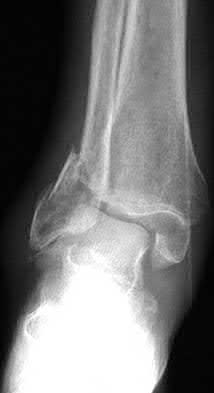

Figure A shows a patient after an open reduction and internal fixation of a bimalleolar ankle fracture.

Egol et al showed that by nine weeks, the total braking time of patients who had undergone fixation of a displaced right ankle fracture returns to the normal, baseline value.

Egol et al, also found that appropriate braking time returns at a point 6 weeks after initiation of weightbearing after treatment of lower extremity long bone and periarticular fractures, as examined with a driving simulator. No differences were seen in return of braking time between periarticular fractures and long bone injuries.